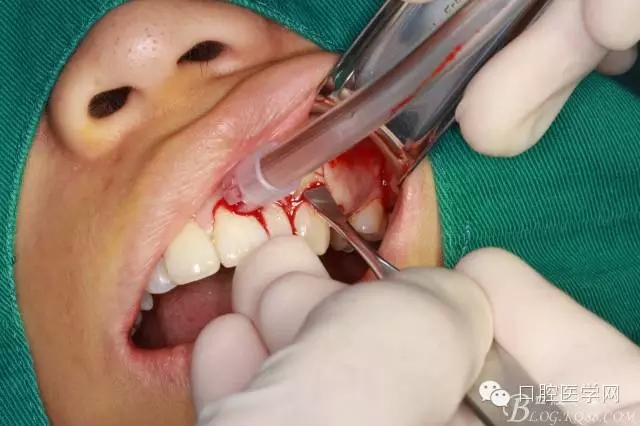

術(shù)前口內(nèi)照

常規(guī)口內(nèi)外消毒鋪巾

局部浸潤麻醉

齦乳頭麻醉

鼻腭神經(jīng)麻醉

垂直切口

水平切口